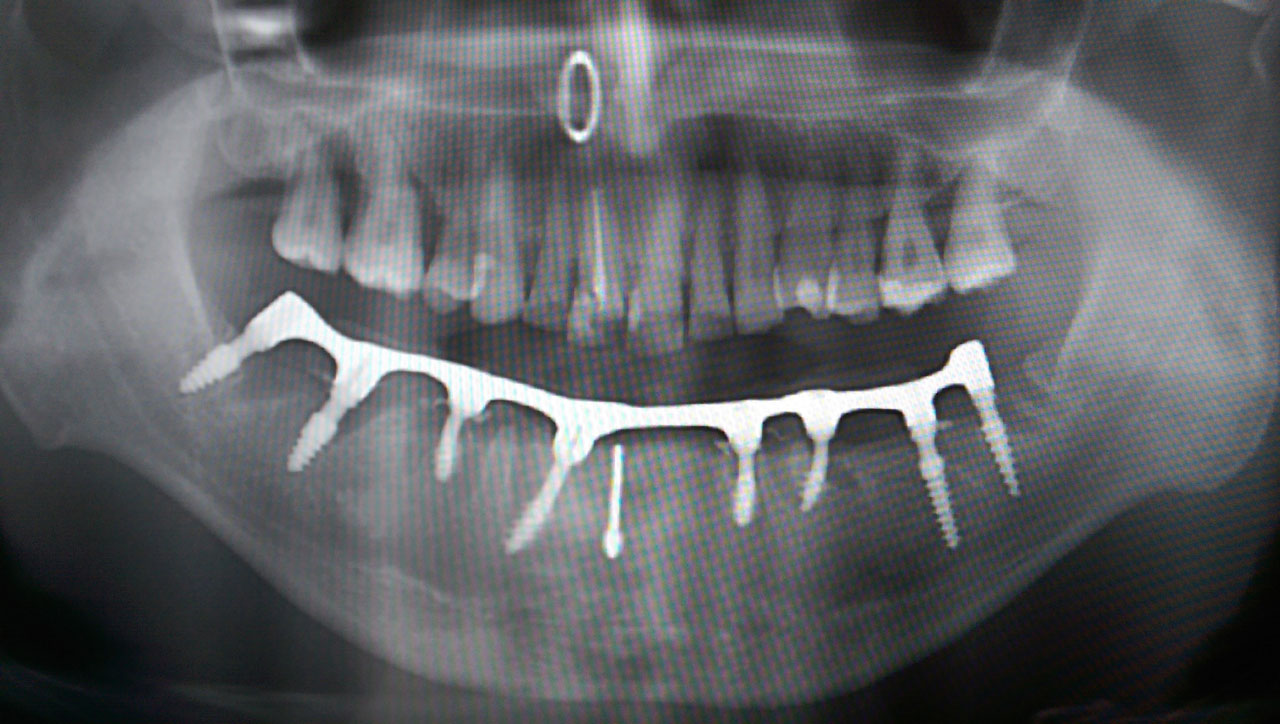

Alsó állcsont teljes rehabilitációja 72 óra alatt

Alsó állcsont teljes rehabilitációja 72 óra alatt, azonnal terhelhető implantátumokkal súlyos paradontitisben szenvedő dohányzó páciens esetében. Az alsó állcsont fogai mind mozogtak az előrehaladott fogágypusztulás miatt.

A fogakat eltávolítottuk, a gyulladt, fertőzött csontot kitakarítottuk, kifertőtlenítettük, majd azonnal implantáltunk.

Svájci, IHDE márkájú, azonnal terhelhető implantátumokat helyzetünk be, és ezekre harmadnapra rögzített, hosszútávú, fémvázas, esztétikus műanyaggal leplezett hidat ragasztottunk be.

Ezt az ideiglenes hidat a sebek gyógyulása miatt használjuk, de tartóssága miatt véglegesként is használható. A legtöbb esetben, ahogy itt is, 6 hónap múlva porcelán hídra cseréljük, a teljes gyógyulás után.